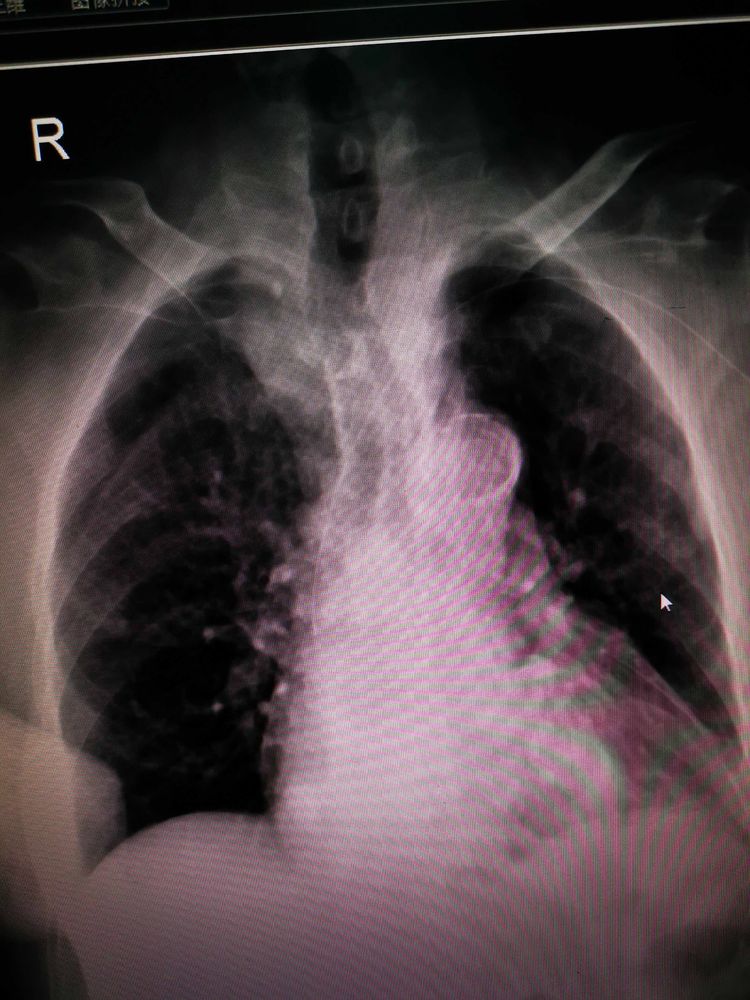

该患者88岁,外周静脉条件差,右手臂外展受限,市三院内二科在谷旭红主任和李艳梅护士长的帮助下,由专科护士宋永向以左手臂贵要静脉为穿刺点、在无菌超声引导下,成功为患者置入pIcc导管,置管后沿静脉走行到上腔静脉并通过拍片确定导管尖端位于T7。填补了市三院内二科pIcc置管技术的空白,标志着市三院内二科护理技术水平迈上了新的台阶。